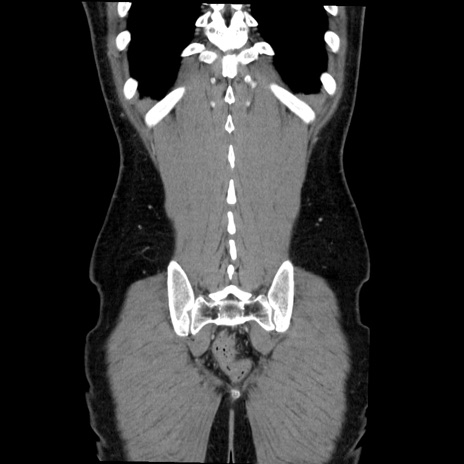

症例36(冠状断像)

【症例】20歳代 男性

【主訴】心窩部痛

【現病歴】今朝より上腹部痛あり。一旦軽快していたが再度出現したため救急要請。昨日夕に白身の魚を含む刺身を食べた。

【身体所見】BP 136/89mmHg、HR 74/min、BT 37.0℃、腹部:膨満、軟、心窩部に圧痛あり。反跳痛なし、筋性防御なし、腸雑音やや亢進あり。

【データ】WBC 17700、CRP 0.48